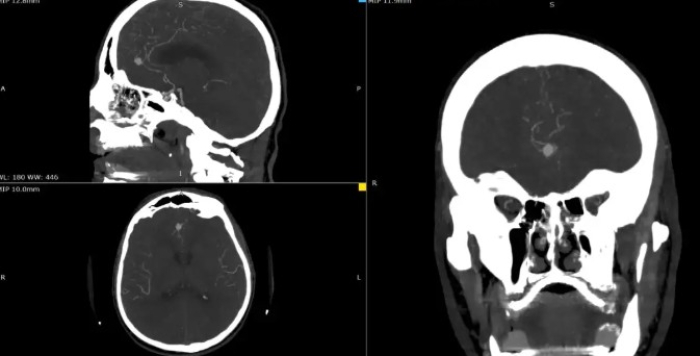

На Неврохирургија првпат применета интраоперативна флуоресцентна видеоангиографија при хируршки третман на мозочна аневризма

На Универзитетска клиника за неврохирургија е извршена комплексна микрохируршка интервенција кај 57-годишен пациент со руптурирана аневризма на мозочен крвен сад.

-Станува збор за операција која за првпат во Македонија е изведена со примена на интраоперативна флуоресцентна видеоангиографија. Оваа иновација е значаен чекор напред во модернизацијата на македонското здравство. Примената на интраоперативната флуоресцентна видеоангиографија ја зголемува безбедноста на пациентите и ја подобрува ефикасноста на хируршките интервенции, вели министерот за здравство Азир Алиу.

Оваа иновативна метода претставува напредна техника која овозможува визуелизација на крвниот проток во реално време за време на операцијата.

-Со примена на контрастно средство, хирурзите можат прецизно да ја проценат проодноста на крвните садови и да го потврдат целосното исклучување на аневризмата, што е клучно за успешен исход, појаснува д-р Благој Шунтов, специјалист по неврохирургија и раководител на тимот.

Операцијата помина без компликации, а пациентот се опоравува без потешкотии. Примената на оваа напредна техника претставува значаен напредок во третманот на неврохируршки пациенти и ја потврдува посветеноста на Клиниката за неврохирургија во примена на најновите медицински технологии.